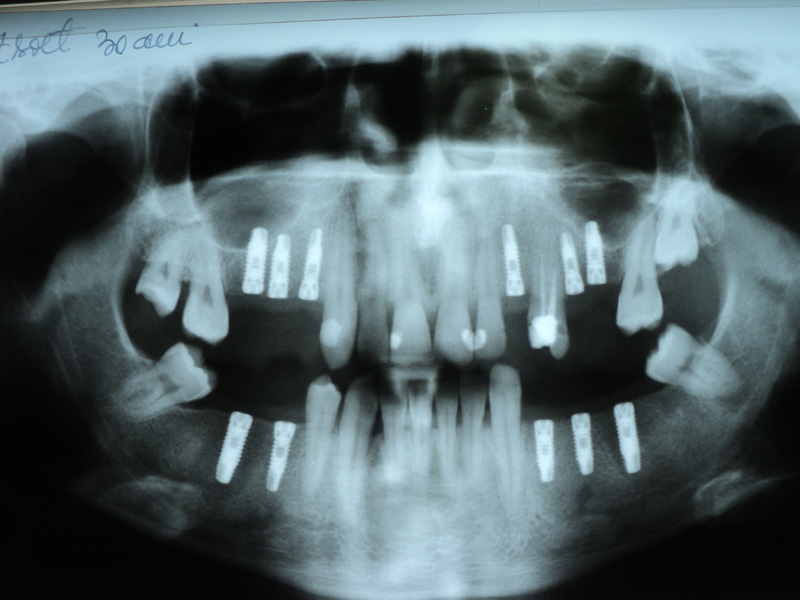

Implante - Galerie Foto

Radio-

grafii